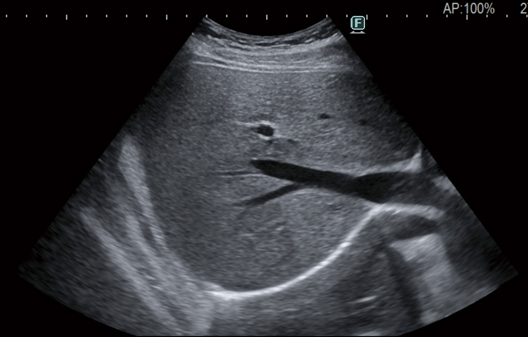

Tecnología de imagen avanzada que produce imágenes con “visibilidad más clara”*. Las imágenes estables con menos dependencia del paciente ayudan a lograr imágenes más claras con menos ruido. Esto es posible gracias a nuestra nueva tecnología de procesamiento de imágenes que mejora la visibilidad de la estructura del tejido.

Como concepto de esta función, nos gustaría poner énfasis en la “visibilidad más clara”.

- * “Visibilidad más clara” debido a la reducción del ruido, la integridad mejorada y la continuidad de los límites de los tejidos.

APAGADO

ENCENDIDO